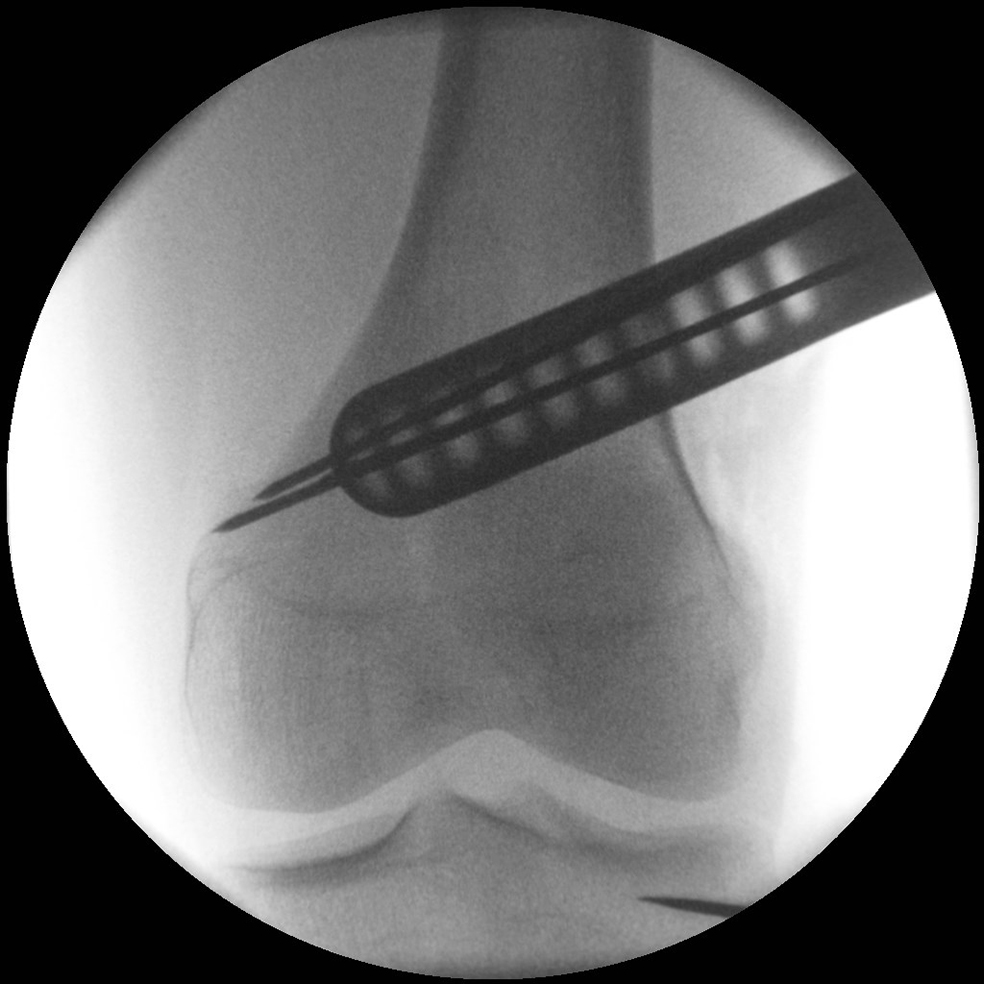

After performing a minimally invasive approach at the medial proximal tibia, the first step of the new K-wire guiding system is definition of the hinge point with a K-wire from the lateral aspect (Fig 11). The guiding arm for the osteotomy was then inserted with the radiolucent hook in situ (Fig 12). The guiding arm should be adjusted under intensifier control and finally fixed with a K-wire. At this stage two K-wires for the osteotomy can be inserted and the guiding arm can be removed. The saw guide is then mounted and guides the sawblade safely (Fig 13 and 14).

The saw guide enables three different angulation options for the ascending cut (Fig 15). Following completion of the osteotomy, the opening is performed in the traditional way using chisel and spreader. Fixation is performed with the new TomoFix MHT Anatomical plate (Fig 16 and 17).